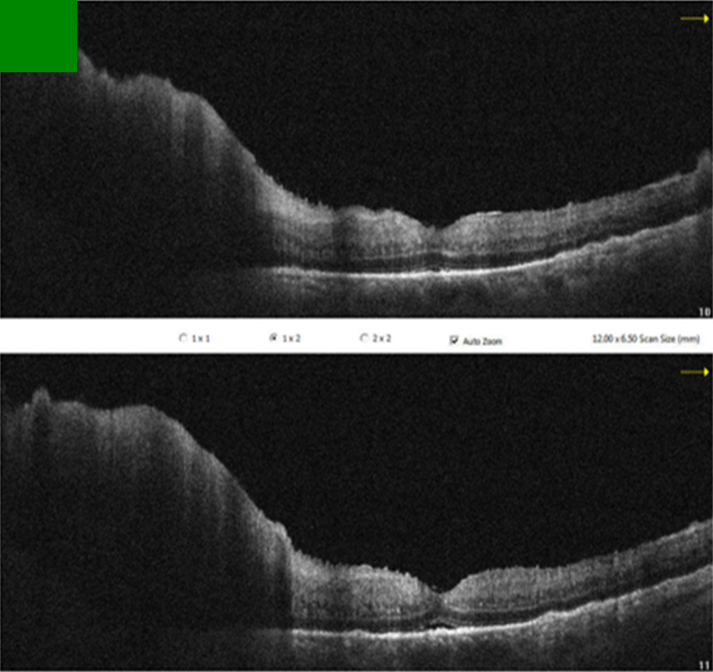

Since the visual acuity decreased to hand motion during systemic investigations, systemic steroid treatment was initiated with isoniazid (INH) prophylaxis. Following treatment, the vitreous inflammation in the left eye improved from +4 to +2 cells, allowing improved visualization of the posterior segment. The optic nerve appeared hyperemic and infiltrated, and the retina demonstrated diffuse white infiltrates with associated generalized retinal thickening, vascular sheathing, and venous beading, predominantly in the left eye (Figure 2 [Fig. 2]). Optical coherence tomography (OCT) showed irregularities and multiple subretinal hyperreflective deposits in the retinal pigment epithelium and Bruch membrane level, which were predominantly present in the left eye and severe optic disc edema (Figure 3 [Fig. 3]). Fundus fluorescein angiography (FFA) revealed indistinct granular changes and mild disc staining in the right eye. Active lesions were characterized by a typical early hypofluorescent pattern observed in the retinal infiltrates, with late hyperfluorescence containing dilated retinal vessels, diffuse pinpoint leakage at the infiltrative border in the left eye and areas of capillary dropout were observed (Figure 4 [Fig. 4]).

Figure 3: Pre-treatment OCT sections of the left eye

OCT revealed irregularities and multiple subretinal hyperreflective deposits at the level of the retinal pigment epithelium and Bruch’s membrane. These irregularities and deposits were predominantly observed in the left eye, accompanied by severe optic disc edema.